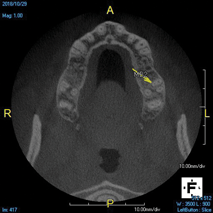

(4.) In a CBCT image axial view, the MB1 and MB2 canals are readily visible in tooth No. 14, and in the coronal view, these two separate canals can be seen to merge into a single apical opening.

Figure 4

Being able to see the number and shape of the canals accurately prior to treatment is the desire of any clinician who performs endodontics. Research suggests that, due to improved diagnostic accuracy, the final treatment plan may change in up to 50% of endodontic cases if CBCT is used rather than traditional 2D imaging.14,15 The question of whether or not a patient has an MB2 canal can be answered prior to opening the access preparation (Figure 4 and Figure 5). Visualizing single canals that bifurcate in the apical or middle third of the root or those that merge to a single apical opening can help clinicians to understand their instrumentation needs in advance. In addition, the ability to measure the length and shape of a canal planned for instrumentation prior to utilizing an apex locator helps to confirm any measurements obtained by other means. It should also be noted that the ability to see a pathosis in 3 dimensions and to involve the patient in understanding his or her condition prior to any decision-making allows for definitive treatment planning. In fact, many patients have pathoses associated with teeth that are asymptomatic that remain unknown to them until they are visually presented with the evidence (Figure 6).